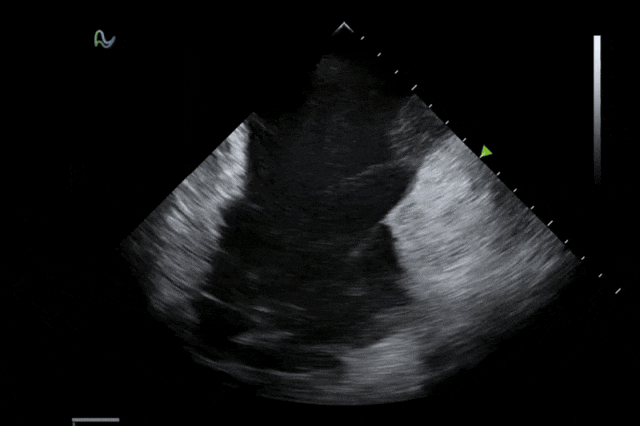

心腔内超声(ICE)被誉为心脏介入手术的"黄金眼",能够顺利获得微创方式实时呈现心脏内部结构和血流成像,为房颤消融、左心耳封堵、先心病介入等手术给予精准成像导航。相较于传统影像手段,ICE具有无辐射、实时成像、操作灵活等显著优势,已成为国际指南推荐的核心诊断技术。

本次获批的ICE导管在全球首次采用了80阵元大孔径高密度探头设计,较传统普通的64阵元产品大幅度提升了成像分辨率、成像深度和图像对比度,可清晰辨识心脏细微结构和血流,为复杂手术给予更可靠的超声成像支持。同时,8F导管凭借更小的外径,显著提升导管顺利获得性和操控性,对病人创伤更小,尤其适合血管条件受限或小心脏患者;10F导管则凭借其优质的成像质量,为复杂心脏介入手术给予精准的影像引导。